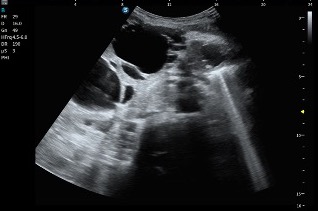

En este caso iniciamos la exploración con sonda convex, siguiendo el protocolo habitual de ecografía abdominal y, al valorar el parénquima hepático, rápidamente llama la atención un hallazgo muy característico que es el que pasamos a describir a continuación.

- Número prácticamente incontable de lesiones

- Morfología redondeada

- Contenido anecoico

- Bordes finos, lisos y bien definidos

El patrón era bastante típico y, según el criterio del radiólogo, correspondía a múltiples quistes hepáticos, como queda reflejado en las imágenes ecográficas (imagen 1 e imagen 2).